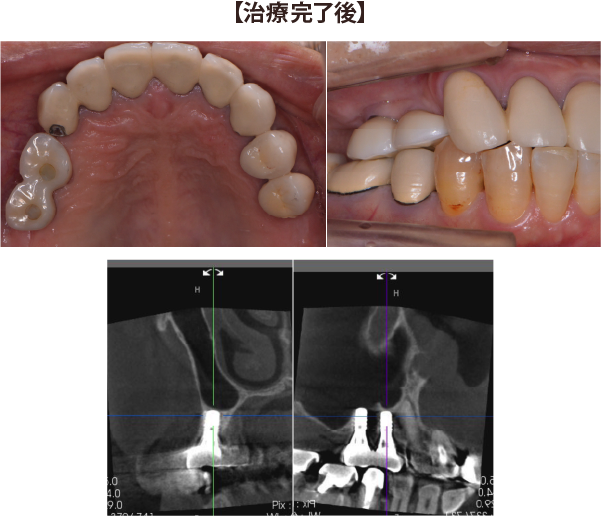

②左上の奥歯2本が無く、インプラントを入れるための骨がほとんど無い症例

左上の歯が無くなった部分に骨の高さが無く、このままではインプラントが骨からはみ出てしまう。

上顎洞底挙上術と人工骨を足す手術を併用し、1回の手術でインプラントを埋入できました。

2ヶ月半ほど骨との結合を待った後に、かぶせ物を製作しています。

埋入から1年後も安定し、骨の高さも維持しています。

全く不安や問題なく、自分の歯のように噛めています。

| 治療期間 : | 3ヶ月 |

| メリット : | ブリッジや入れ歯に比べて、両隣の歯を削ること無く、強い歯を再建することができる。 入れ歯やブリッジに比べて自然なかみ合わせを得られる。 概して入れ歯やブリッジより長持ちし、他の残存歯における負担も減らすことで、残存歯本来の寿命を全うできることが多い。 虫歯にならない。 |

| リスク・副作用 : | 手術が必要であり、感染のリスクを伴う。 術後に一時的に腫れたり痛みが出ることがある。 治療完了までに数か月の期間を要する。 自費治療であり、保険治療より高額である。 |

| 費用(自費治療分): | 合計金額 ¥1,023,000(税込) (ソケットリフト法×2、人工骨使用、SLActive加算×2、ジルコニア冠の場合) |